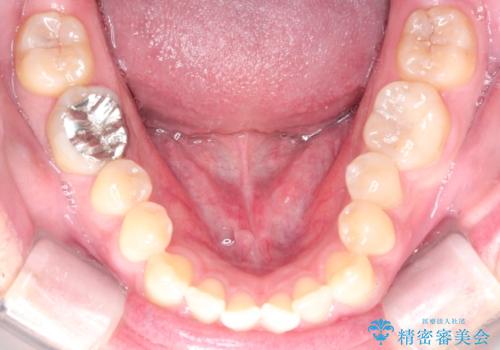

- 前歯の咬み合わせが気になるとのことで来院されました。

前歯が噛んでいない状態(開咬)のため、インビザライン矯正で改善することとしました。

前歯が嚙んでない場合(開咬)、顎間ゴムというゴムを使用してもらうことがあります。顎間ゴムは、前歯を噛み合わせるための力を与える補助的な役割があります。